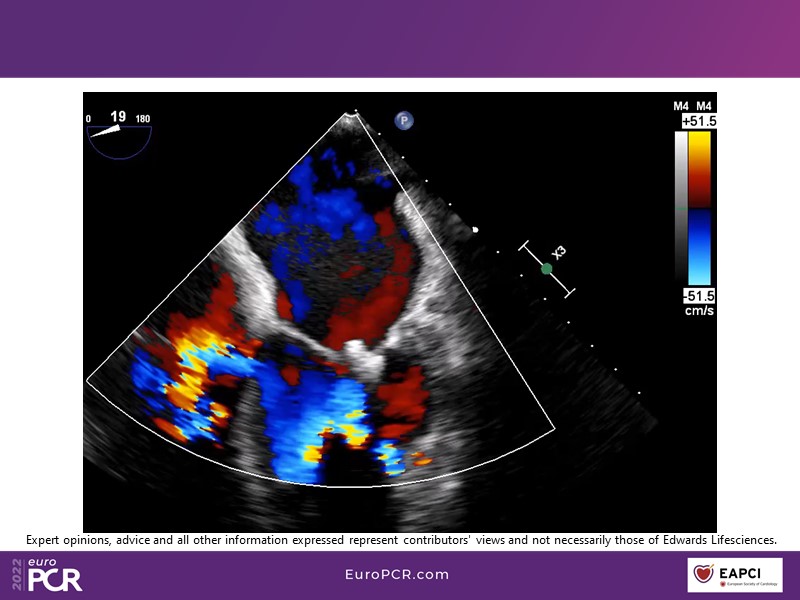

With study outcomes and clinical cases, this EuroPCR 2022 session will enable you to discuss the anatomical considerations that define suitable candidates for treatment of mitral regurgitation with the PASCAL platform and highlight key differentiators and tips and tricks for its use.

- To discuss which anatomical considerations define suitable candidates for the treatment of mitral regurgitation with the PASCAL platform

- To attend case-based discussions that will highlight key differentiators and tips and tricks when using the PASCAL platform to treat mitral regurgitation